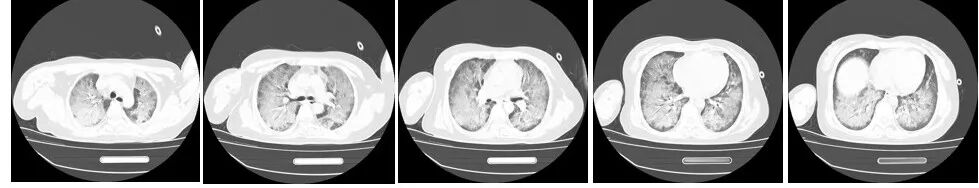

图2(2024年9月20日 D4)胸部CT双肺弥漫性渗出性改变,伴磨玻璃影较前增多。